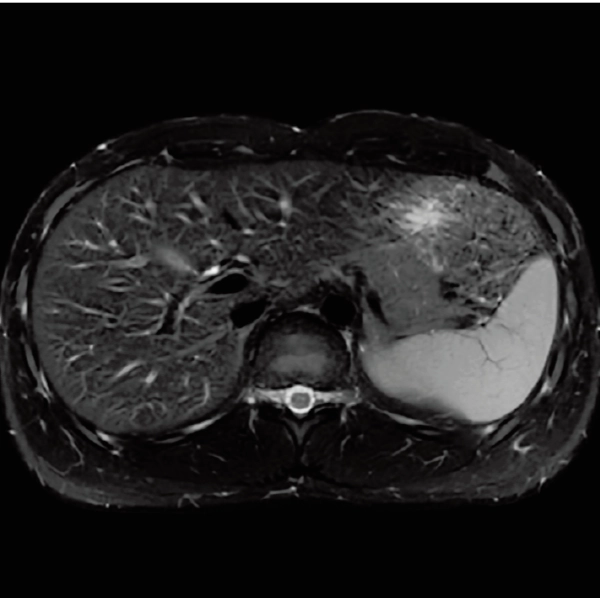

RADAR:Body movement suppression technology for those who cannot hold still

T2*WI RADAR, 2:34

T2WI FatSat Respiratory gating RADAR, 2:16